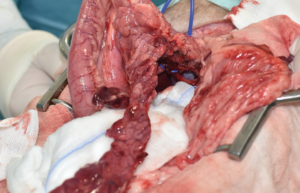

La cirugía de elección es la pancreatectomía parcial y la resección de losnódulos linfáticos (NNLL) centinelas (imágenes 3A-3I). La quimioterapia intracavitaria puede controlar la efusión por carcinomatosis secundaria, pero ofrece una respuesta paliativa de corta duración. La pancreatectomía completa o pancreaticoduodenectomía (técnica de Whipple), descritas en el perro, presentan altas tasas de morbilidad y mortalidad operatorias. La técnica de Billroth II es una opción paliativa a corto plazo en casos de obstrucción intestinal. En un estudio retrospectivo en 34 pacientes felinos con carcinoma pancreático exocrino primario la enfermedad se asoció con una historia previa de diabetes mellitus.35 El carcinoma pancreático exocrino canino se caracteriza por una alta tasa de metástasis y un pronóstico grave general.37

Imágenes 3A – 3I. Secuencia de imágenes quirúrgicas en un perro (con las imágenes del TC), durante una pancreatectomía parcial del lóbulo izquierdo y cuerpo del páncreas, usando un sellador vascular/tisular, por carcinoma pancreático.

El tratamiento quirúrgico es el de elección para perros con enfermedad en estadio I (enfermedad localizada) o II (presencia de metástasis locorregional) e implica una pancreatectomía parcial para extirpar el tumor primario y cualquier metástasis visible (imágenes 4A-4K y 5A-5H). La mediana de supervivencia es más larga en los perros tratados quirúrgicamente en comparación con los perros tratados médicamente, como se describe en dos estudios donde la mediana del tiempo de supervivencia de los perros sometidos a pancreatectomía parcial fue de 381 días y 785 días, respectivamente, en comparación con 74 días y 196 días, respectivamente, en aquellos tratados solo con tratamiento médico.30 En otro estudio reciente, el tiempo medio de supervivencia registrado para 49 perros con insulinoma fue de 561 días y de hasta 746 días para perros que tuvieron resolución de hipoglucemia, con un tiempo medio euglucémico global (tiempos desde la cirugía hasta la primera detección de hipoglucemia en cualquier momento después de la cirugía) de 424 días para todos los perros.39

Imágenes 4A – 4K. Secuencia de imágenes quirúrgicas en un perro (con las imágenes del TC), durante una pancreatectomía total del lóbulo izquierdo y cuerpo del páncreas (usando la técnica de “guillotina” sutura/fractura con el nudo de Miller modificado) y resección de NNLL centinelas, por insulinoma en el cuerpo del páncreas.